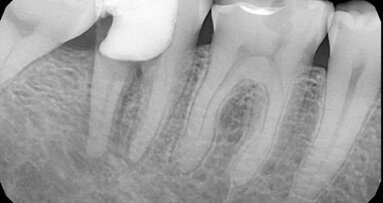

Cilj endodontskog tretmana je spriječavanje inflamacije i postizanje produženog efekta procedure. Kako bi se ovo postiglo, veoma je važno primjeniti ...